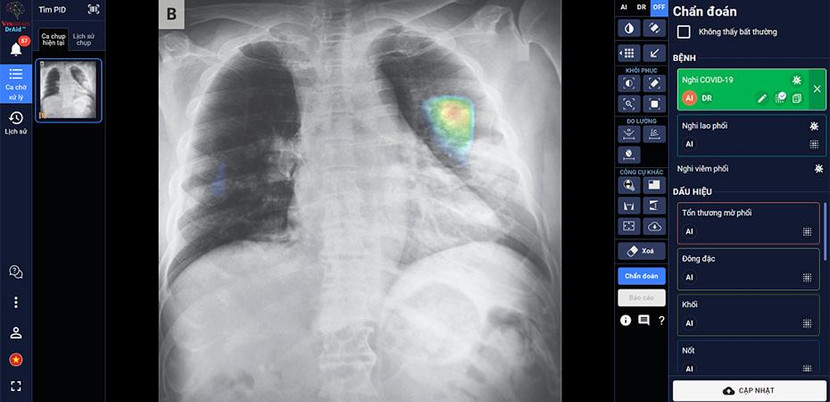

DrAid™ – phần mềm AI trợ lý bác sĩ đầu tiên tại Việt Nam - do các chuyên gia, nhà khoa học của VinBrain (công ty công nghệ thuộc Tập đoàn Vingroup) nghiên cứu phát triển thành công. DrAid hiện có khả năng hỗ trợ chẩn đoán 20 dấu hiệu bất thường và bệnh lý về tim - phổi - xương với độ chính xác trên 88% trong vòng 5 giây, đồng thời tự động đưa ra báo cáo y tế theo chuẩn quốc tế JCI có khoanh vùng và đo kích thước chính xác tại khu vực bất thường.

Đặc biệt, DrAid™ mang lại 4 giá trị ưu việt trong phát hiện và điều trị COVID-19 dựa trên ảnh X- quang ngực thẳng gồm: Phát hiện nhanh góp phần sàng lọc mầm bệnh trong cộng đồng, song song cùng phương pháp xét nghiệm PCR. Kết hợp cùng xét nghiệm PCR từ đó nâng cao độ chính xác, giảm thiểu tình trạng âm tính giả tránh bỏ sót; Hỗ trợ đánh giá tiên lượng tình trạng bệnh nhân thông qua lịch sử hình ảnh chụp X-quang, để từ đó có hướng điều trị phù hợp; Hỗ trợ tăng tính nhất quán và chuyển giao kiến thức của bác sĩ từ tuyến Trung ương tới cơ sở.

![]() |

| DrAid™ chẩn đoán và tiên lượng điều trị bệnh nhân COVID-19 dựa trên hình ảnh X-quang ngực thẳng |